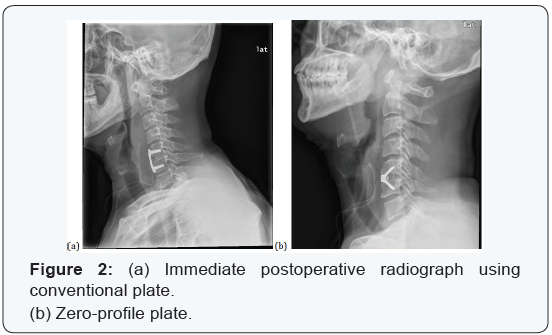

Before the introduction of zero-profile plate on February 2011, a conventional plate (Vectra-T plate, Synthes, Switzerland) was used and ever since, zero-profile plate (Zero-P plate, Synthes, Switzerland) was used for degeneration cases (Figure 2). For postoperative care, soft cervical collar (Philadelphia brace) was applied for 1 day and then all neck motion was allowed without brace. Conventional radiograph was performed on the final follow up for each case (Figure 3). To eliminate the difference of loading due to difference numbers of fused segment, multi segment fusion cases were excluded from the study. In addition, since compromised soft tissues such as anterior longitudinal ligament and bony structures could accelerate degeneration of the adjacent segment, trauma or tumor cases were also excluded [11,12]. Also, cases without radiological follow up at least 12 months after surgery were not included.